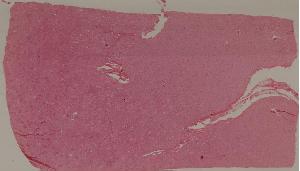

74.新月体性肾炎

低倍视野